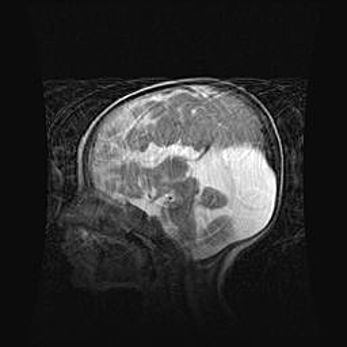

Церебральная ишемия II.

Возраст: 5 дней

Вес: 3400 г

Пол: женский

Окружность головы: 35 см

Срок гестации: 39 недель

Церебральная ишемия – это заболевание, характеризующееся недостаточностью (гипоксией) либо полным прекращением (аноксией) снабжения мозга кислородом по причине закупорки одного или нескольких сосудов. Это приводит к  что метаболическим расстройствам различной степени тяжести в тканях головного мозга, развитию коагуляционных некрозов и гибели нейронов.